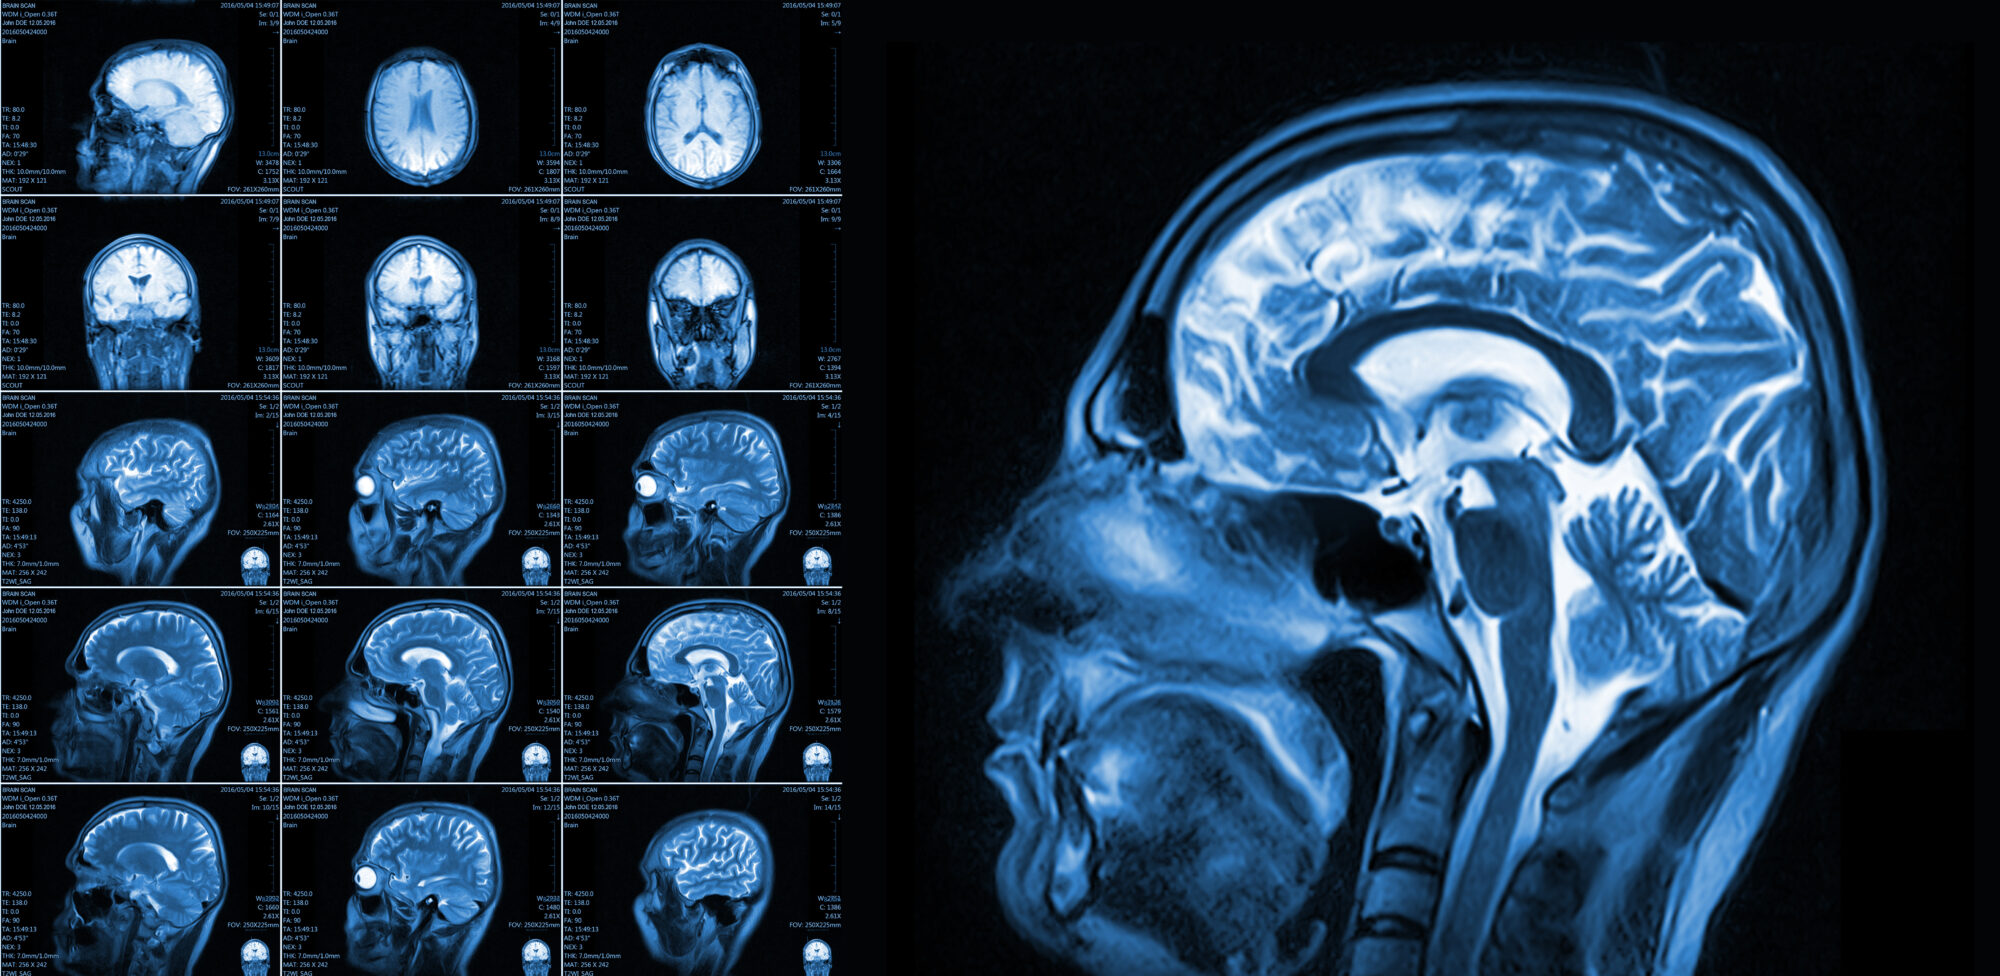

March, designated as Brain Injury Awareness Month, serves as a crucial opportunity to shed light on the impact of brain injuries, advocate for proper screening, and emphasize the significance of legal representation for those affected. Let’s delve into the importance of this awareness campaign and how Brubaker Injury Law stands at the forefront of brain injury cases.

Brubaker Injury Law recognizes the profound impact of brain injuries.